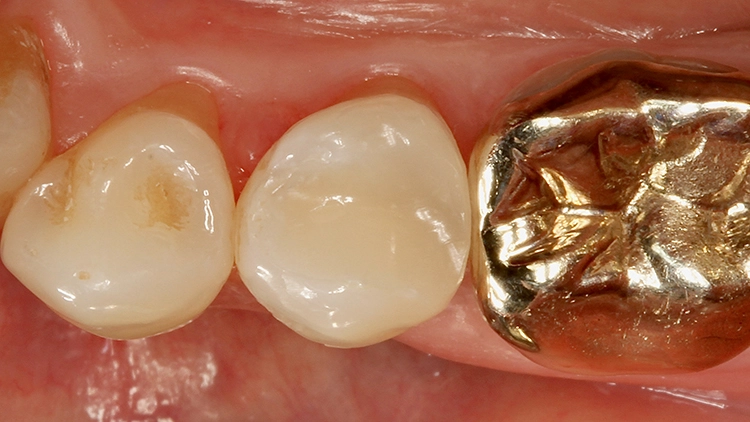

Der 55-jährige Patient störte sich an dem Randausbruch seines erst 10 Jahre alten Keramikinlays an Zahn 45 (Abb. 7). Er wünschte eine Neuversorgung mit Keramik. Nach eingehender Aufklärung und Beratung konnte er davon überzeugt werden, dass in der Dimension der Kavität eine direkte Kompositversorgung genauso funktionieren könnte.

Der sehr anspruchsvolle Patient haderte zunächst wegen der Ästhetik von „Kunststofffüllungen“: Er war der Überzeugung, dass hier keine adäquate Farbanpassung möglich sei, ließ sich aber auf den Vorschlag der direkten Kompositversorgung ein. Dieser Fall sollte dann eine Challenge für die Universalfarbe Venus Diamond One werden – aufgrund vorangegangener guter Erfahrungen von über 1,5 Jahren mit dem Material [10] konnte man sich ziemlich sicher sein, dass hier automatisch eine adäquate Farbanpassung stattfinden wird und gar keine hochspezifische individuelle Zahnfarbbestimmung erforderlich ist.

Die weitere Versorgung der Kavität erfolgte analog zu Fall 1 nach Anwendung eines klassischen Etch&Rinse-Mehrflaschenadhäsivs und schichtweiser Applikation und Polymerisation von Venus Diamond ONE (Kulzer) mit einem Hochleistungs-LED-Polymerisationsgerät > 1.000 mW/cm2 für jeweils 20 Sekunden Lediglich anstelle des Venus Diamond Flow Baseliners kam aufgrund der sehr hohen ästhetischen Ansprüche des Patienten Venus Diamond Flow in der Farbe A2 zum Einsatz – der Patient hätte keinen weiß-opaken Rand an seiner Restauration akzeptiert. Das Ergebnis (Abb. 9) überzeugte den Patienten nicht nur funktionell, sondern vorrangig ästhetisch: Auch hier passt sich die Universalfarbe perfekt an die Zahnhartsubstanz an. Zur Überprüfung der Ausdehnung der Überkappung wurde im Anschluss an die Versorgung eine Zahnfilm-Röntgenaufnahme erstellt (Abb. 10).